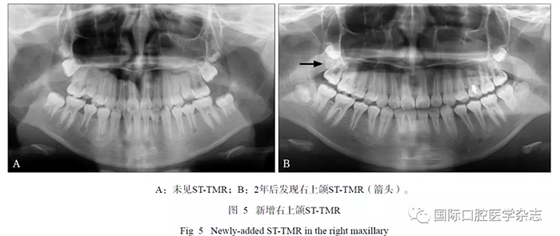

在17例有隨訪拍片的患者中,2例新增STTMR,其中1例患者第一、第二次拍片年齡分別為10歲、13歲(間隔2年7個(gè)月),另1例患者第一次、第二次拍片年齡分別為9歲、11歲(間隔2年,圖5);1例發(fā)生位置改變,ST-TMR由上頜第三磨牙方向近中移動(dòng)(間隔2.5年,圖6)。

本研究對(duì)影像系統(tǒng)中的資料進(jìn)行連續(xù)觀察,可觀察到ST-TMR的病例中最小年齡為11歲(3例),并分析對(duì)比2例追蹤發(fā)現(xiàn)新增ST-TMR的女性青少年患者前后2次拍片的年齡,推測(cè)上頜STTMR的出現(xiàn)可能約在10歲后,略晚于第三磨牙(8~11歲),這種影像表現(xiàn)的時(shí)間順序是否為普遍規(guī)律,仍需進(jìn)一步觀察研究。